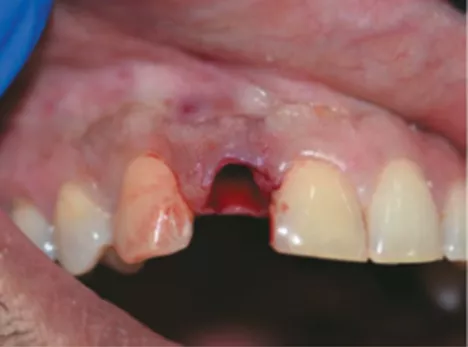

PTQSF_05

FIG 5:

The extraction socket just after extraction of tooth #12. There was no buccal cortical bone. Curettage was performed to remove perapical cyst and granulation tissue. PRF grafting was done for better tissue healing and one week’s waiting time was observed post extraction.